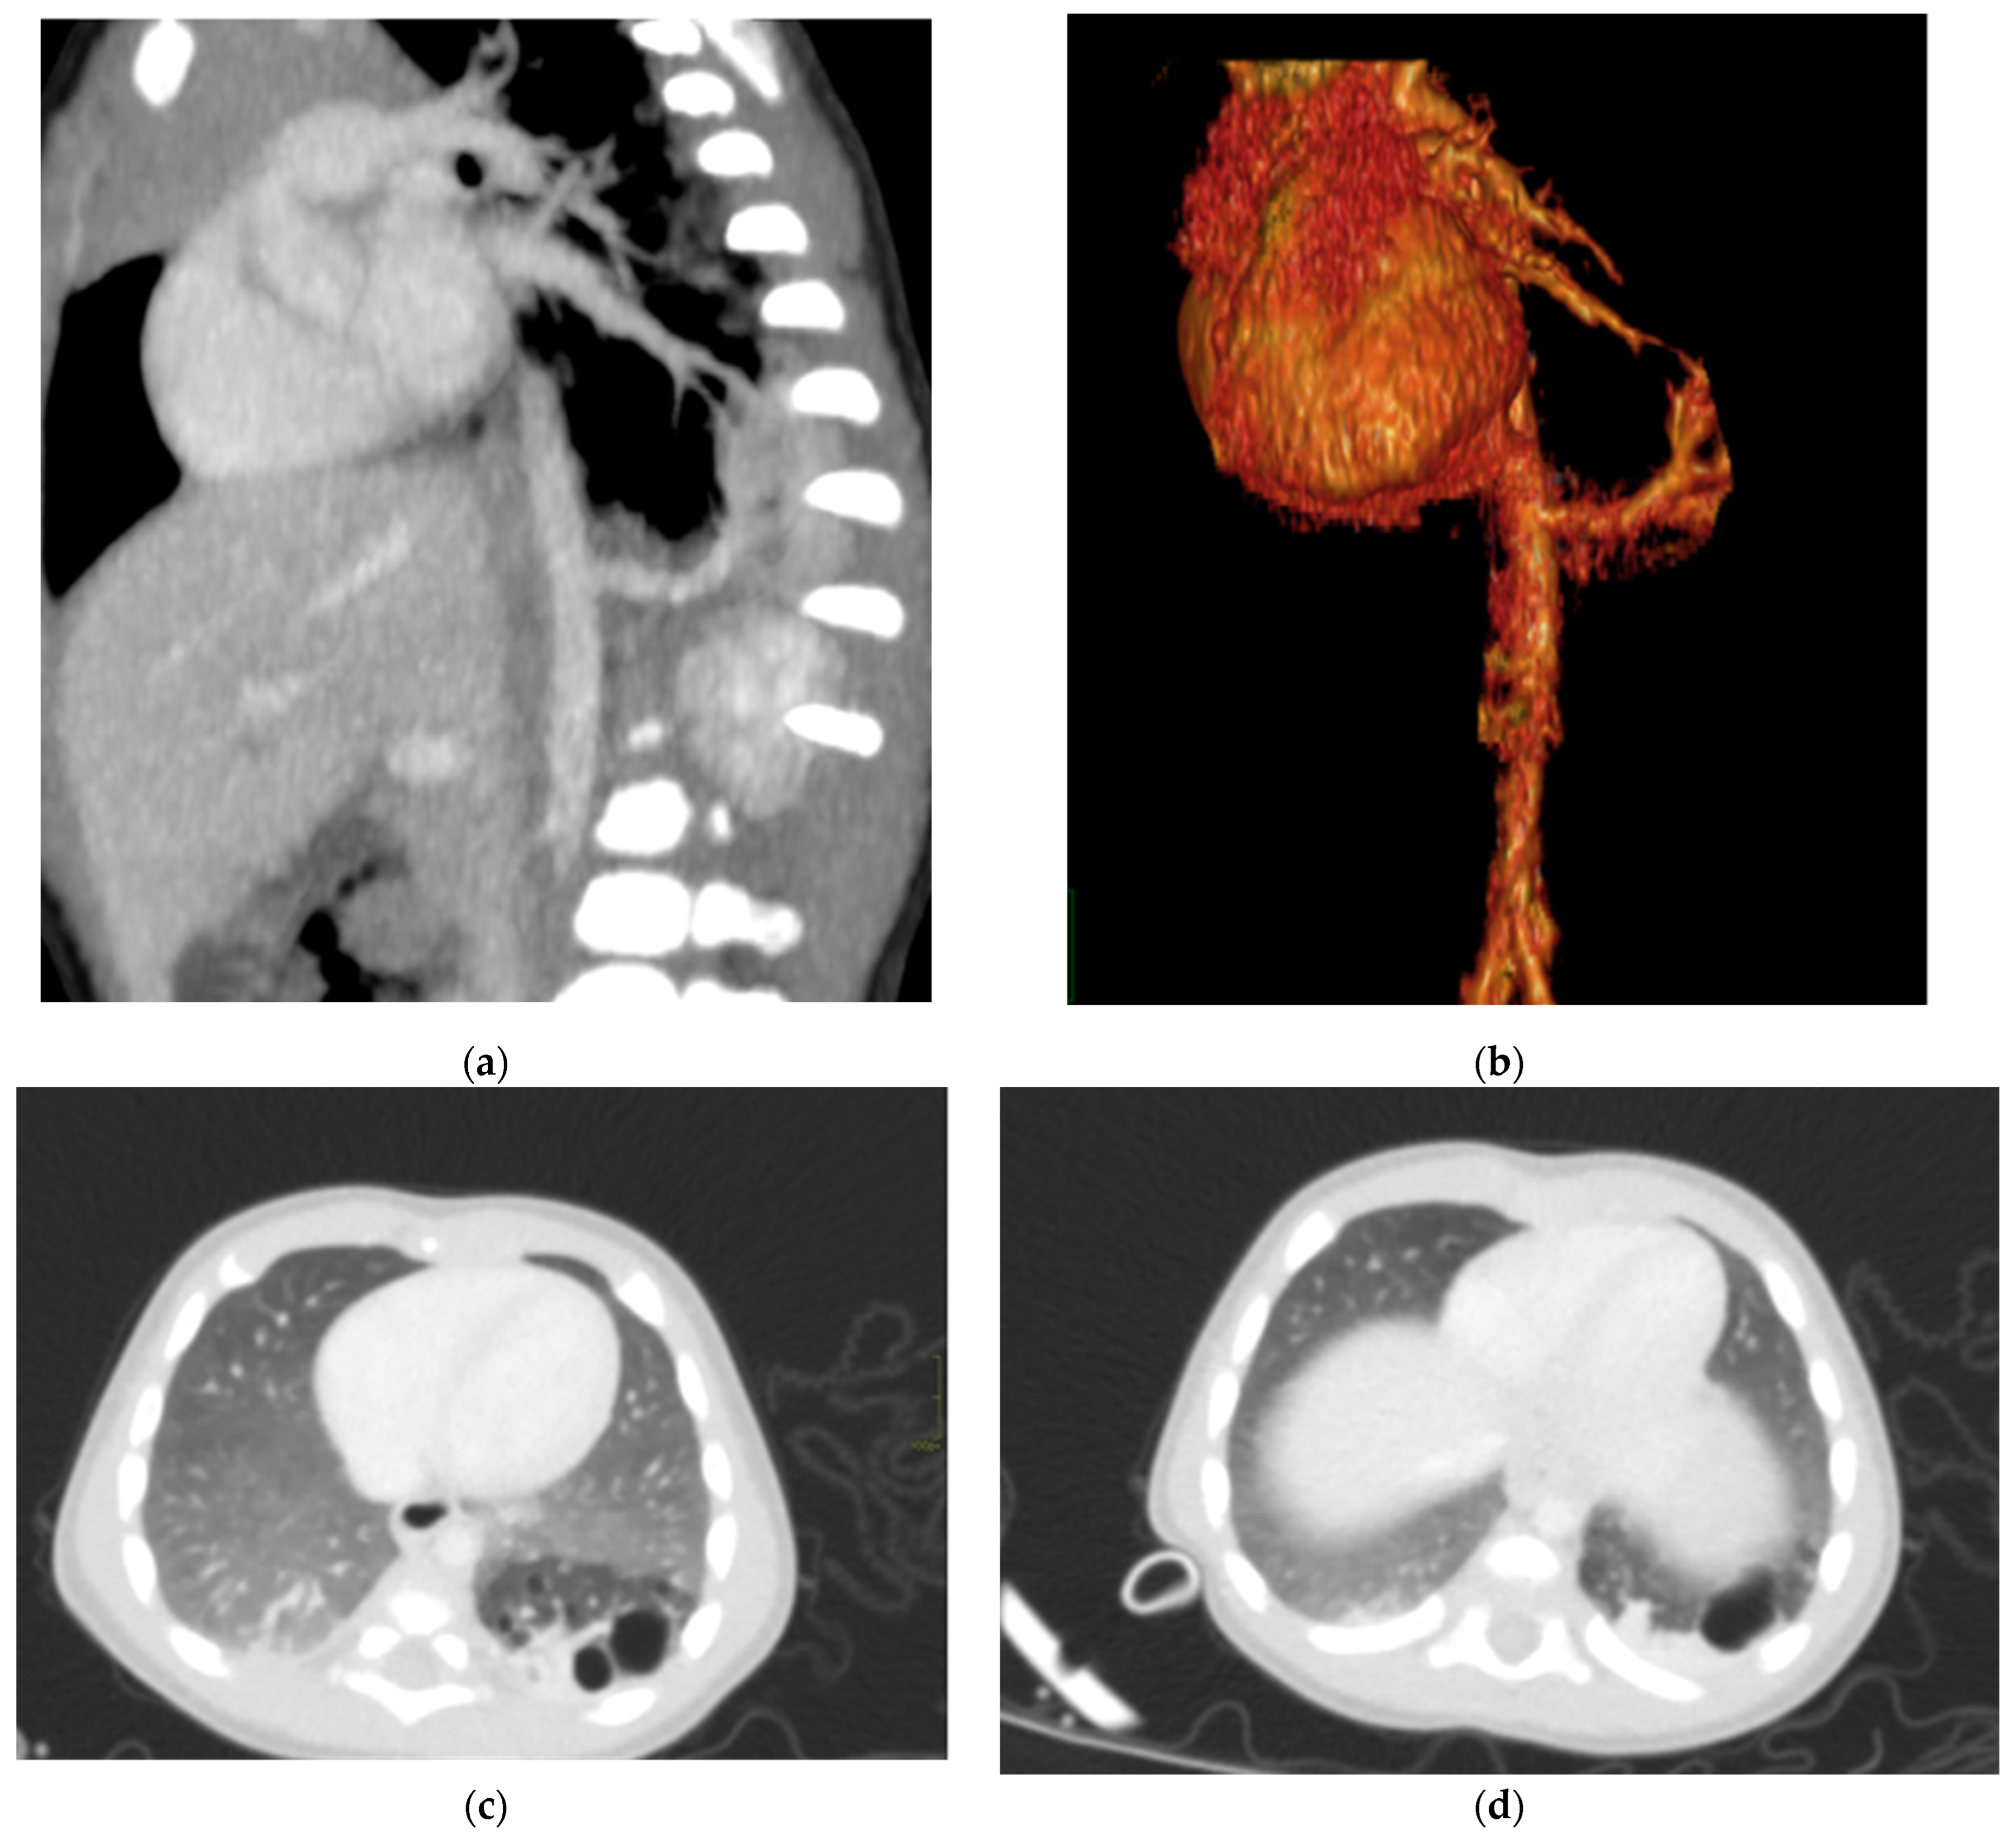

Figure 6. Hybrid congenital malformation consisting of lung seizure and CCAM. CECT MPR reconstruction (a), VR (b), and axial (c,d) images show the presence of a lobulated-margin formation located in the lower lobe of the left lung, which is consists of multiple cystic formations (diameters ranging between a few millimeters and 1.5 cm) and a consolidation zone corresponding the costodiaframmatic recess, which is supplied by a voluminous arterial branch originating from the left lateral wall of the aorta in the thoraco-thoracic passage.

In terms of location, about 85–90% of sequestrations are supradiaphragmatic, with the remaining 10–15% being subdiaphragmatic [11]. Approximately 90% of sequestrations are located on the left side. The systemic arterial supply typically comes from both the lower thoracic and upper abdominal aorta (Figure 6).